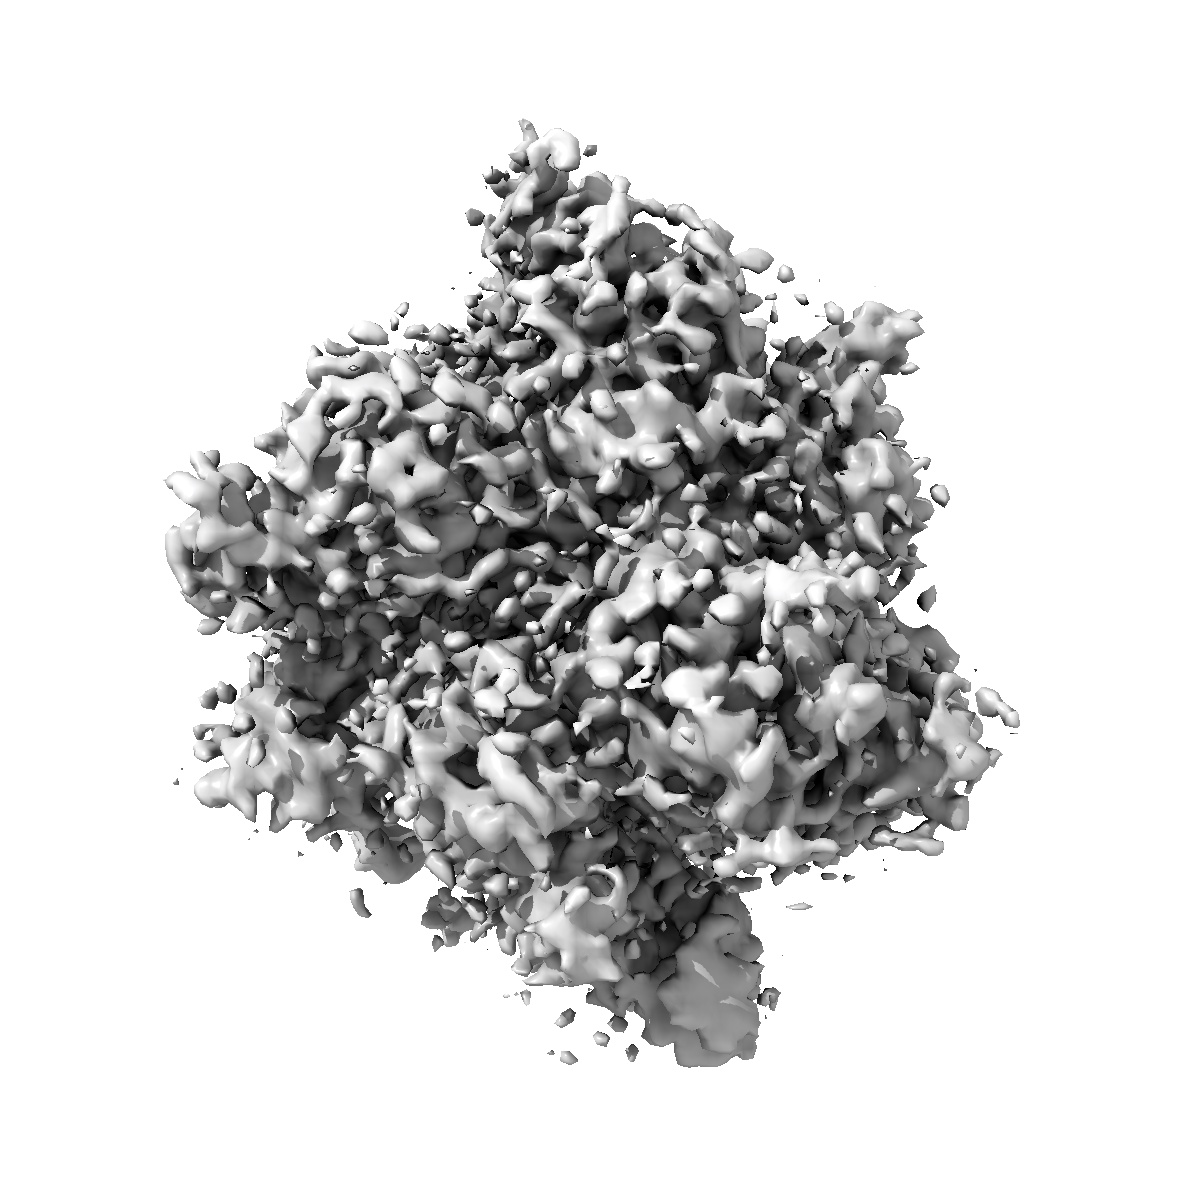

Cryo-EM structure of Fas-FADD complex

Sample: Human Fas-FADD DD complex

Fitted models: 9ncq

Assembly and activation of the death-inducing signaling complex.

Fosuah E , Shen Z , Xie J , Wang C , Lin Q, Fu TM

(2025) PNAS , 122 , e2504819122 - e2504819122